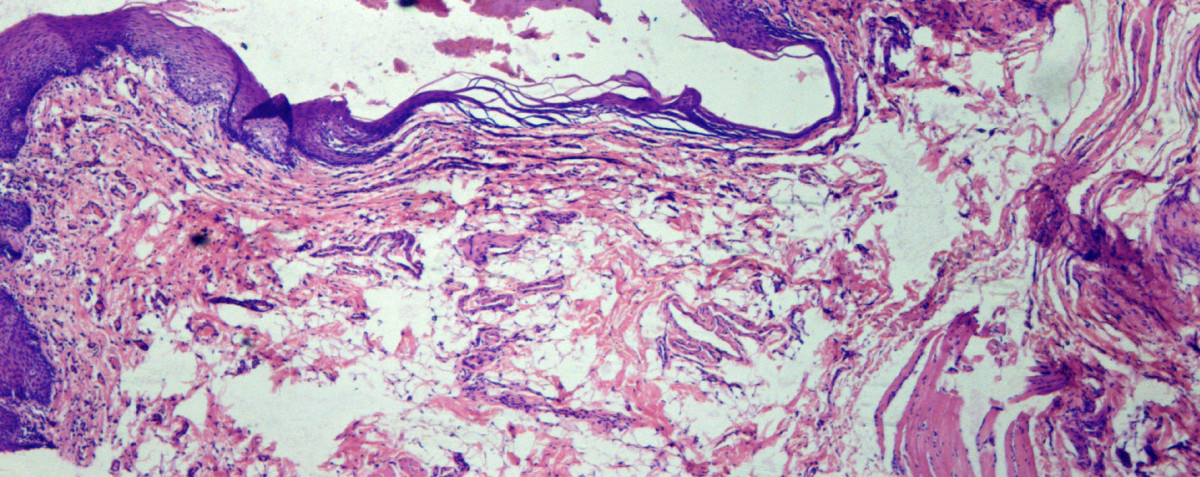

Of the 79 patients, 31 had abnormal brush biopsy results (Figure 3) and of these, histology from 26 cases was positive for either dysplasia or carcinoma. The positive predictive value of an abnormal brush biopsy, defined as a measure of the likelihood that a patient with an abnormal brush biopsy will have a histologic report of dysplasia or carcinoma on follow-up scalpel biopsy was 83.7% (26/31) and the negative predictive value was 98% (47/48).

Figure 3. Panorama of atypical and malignant cells identified from a brush biopsy specimen with the aid of a highly specialized neural network-based image-processing system.

(Pap × 1000).